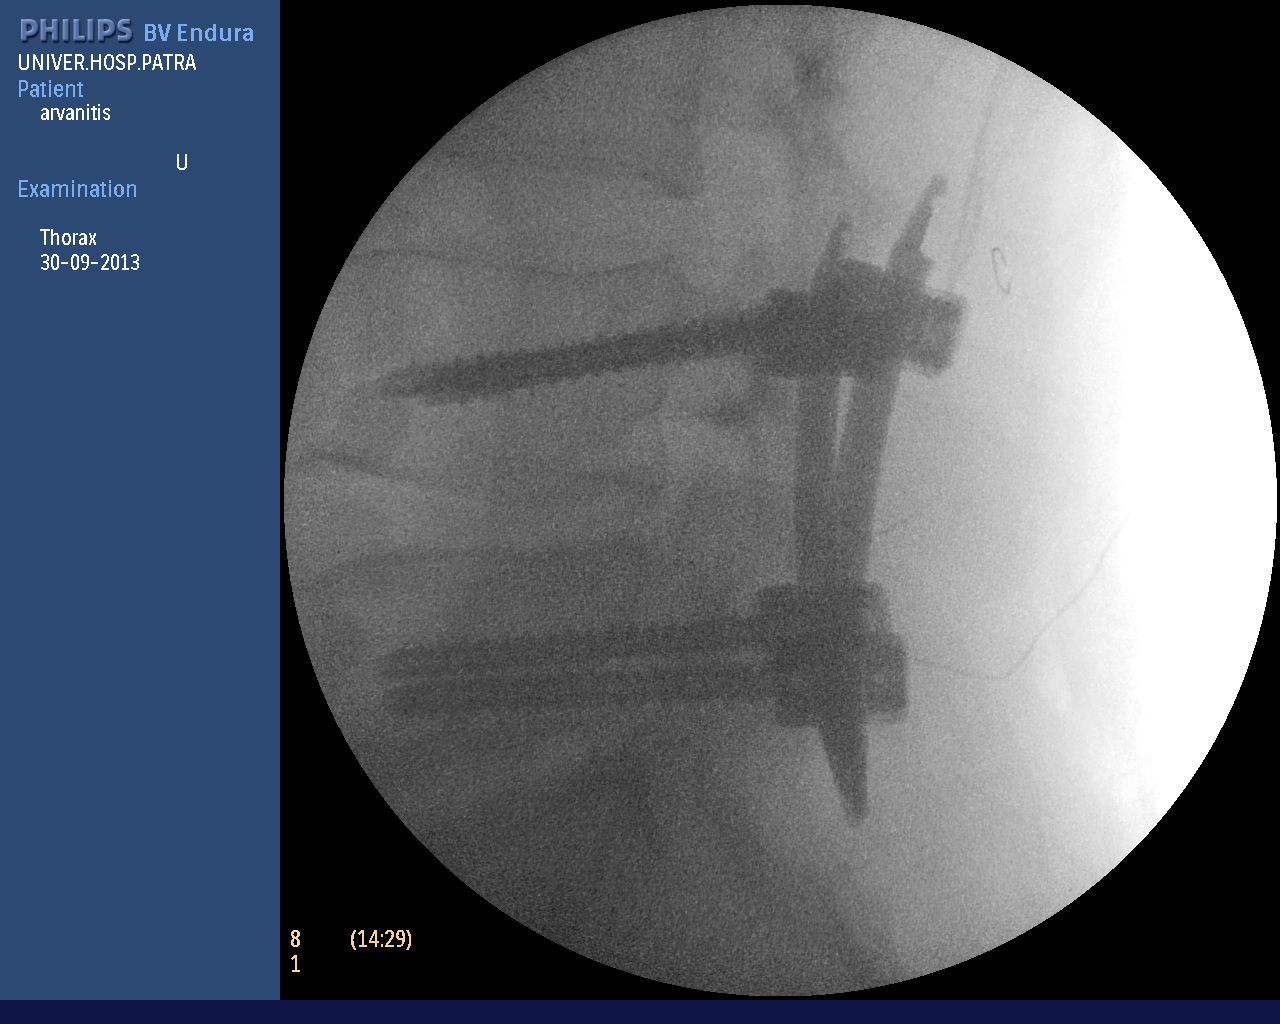

In more complex spinal problems (vertebral fractures, spondylolisthesis, instability, etc.), spinal fusion is needed, i.e. the placement of special screws and rods to stabilize the vertebrae. The operation is also performed percutaneously, avoiding tissue injury and postoperative pain. As shown in the photos (personal file) wire guides are placed and with the help of neuroplasty the screws are implanted if necessary. In every phase of the surgery the neurosurgeon sees the anatomical structures on the monitor accurately and avoids any tissue injuries.

The photographs illustrate the transdermal placement of the materials using the neuropilot which allows on-line observation of the surgeon's movements with millimetre precision.

Intraoperative radiography of percutaneous spinal fusion.

Intraoperative image of percutaneous spinal fusion surgery for dislocation of the th10 vertebra.